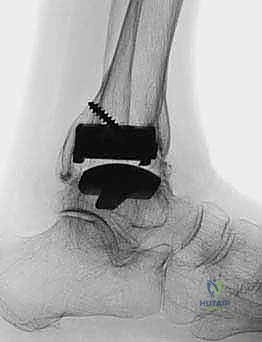

استبدال مفصل الكاحل الكلي بنظام TNK لعلاج خشونة الكاحل المتقدمة

استبدال مفصل الكاحل الكلي هو إجراء جراحي فعال يعالج خشونة الكاحل والتهاب المفاصل الروماتويدي في مراحلهما النهائية، باستخدام نظام TNK المبتكر لاستعادة وظيفة المفصل وتخفيف الألم بشكل دائم. يقدم الأستاذ الدكتور محمد هطيف هذا العلاج المتطور في صنعاء، مع التركيز على التخطيط الدقيق والتقنيات الجراحية المتقدمة لضمان أفضل النتائج للمرضى.

الخلاصة الطبية الشاملة: يُعد استبدال مفصل الكاحل الكلي (Total Ankle Arthroplasty - TAA) ثورة طبية حقيقية وإجراءً جراحياً بالغ الفعالية لعلاج حالات خشونة الكاحل المتقدمة والتهاب المفاصل الروماتويدي في مراحلها النهائية. من خلال استخدام نظام TNK المبتكر، يتم استعادة الوظيفة الحركية للمفصل وتخفيف الألم المزمن بشكل دائم، مما يعيد للمريض جودة حياته المفقودة. يقود هذا التطور الطبي في اليمن الأستاذ الدكتور محمد هطيف، أستاذ جراحة العظام والمفاصل بجامعة صنعاء، والذي يمتلك خبرة تتجاوز 20 عاماً. يرتكز الدكتور هطيف في ممارسته على الأمانة الطبية الصارمة، والتخطيط الجراحي الدقيق، مستخدماً أحدث التقنيات العالمية مثل الجراحة الميكروسكوبية، ومناظير المفاصل بتقنية 4K، والمفاصل الصناعية الحديثة لضمان تحقيق أعلى نسب النجاح العالمية لمرضاه في صنعاء.

لماذا نظام TNK؟ ثورة في المفاصل الصناعية

يُعد اختيار نوع المفصل الصناعي قراراً حاسماً. يفضل الأستاذ الدكتور محمد هطيف استخدام نظام TNK (وأنظمة مشابهة من الجيل الحديث) لعدة أسباب علمية وهندسية قوية:

- التثبيت بدون أسمنت عظمي (Cementless Fixation): تعتمد مكونات نظام TNK على طلاء خاص (غالباً من التيتانيوم المسامي أو الهيدروكسي أباتيت) يسمح للعظم الطبيعي بالنمو والاندماج المباشر مع المعدن (Osseointegration). هذا يوفر تثبيتاً بيولوجياً قوياً وطويل الأمد يقلل من احتمالية تخلخل المفصل بمرور الوقت.

- تصميم يحاكي التشريح (Anatomic Design): كما ذكرنا سابقاً، الميلان الخلفي بمقدار 10 درجات في المكون الظنبوبي يعكس التشريح الطبيعي بدقة، مما يحسن من استقرار المفصل ونطاق حركته.

- مواد عالية التحمل: يتكون المفصل من سبائك معدنية فائقة القوة (مثل الكوبالت كروم أو التيتانيوم) مع حشوة بلاستيكية طبية متطورة (Highly Cross-linked Polyethylene) تقاوم التآكل بشكل استثنائي.

5. زراعة نظام TNK النهائي

بمجرد التأكد من المقاسات والزوايا المثالية، يتم زرع المكونات النهائية. يتم إدخال المكون الظنبوبي المعدني بقوة ليثبت في العظم، يليه المكون الكاحلي. أخيراً، يتم إدخال الح